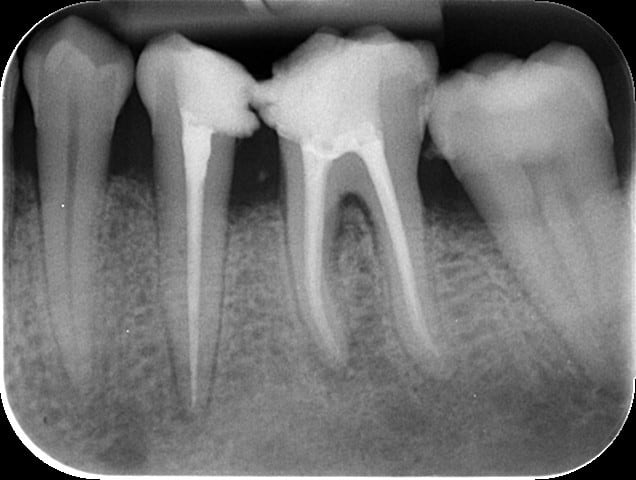

Ca y est, c'est fait.... Un beau morceau quand même, dégoutée...

Donc méfiance avec le QS sur les gros fumeurs et pas de 1/100 000e. J'ai retenu la leçon!